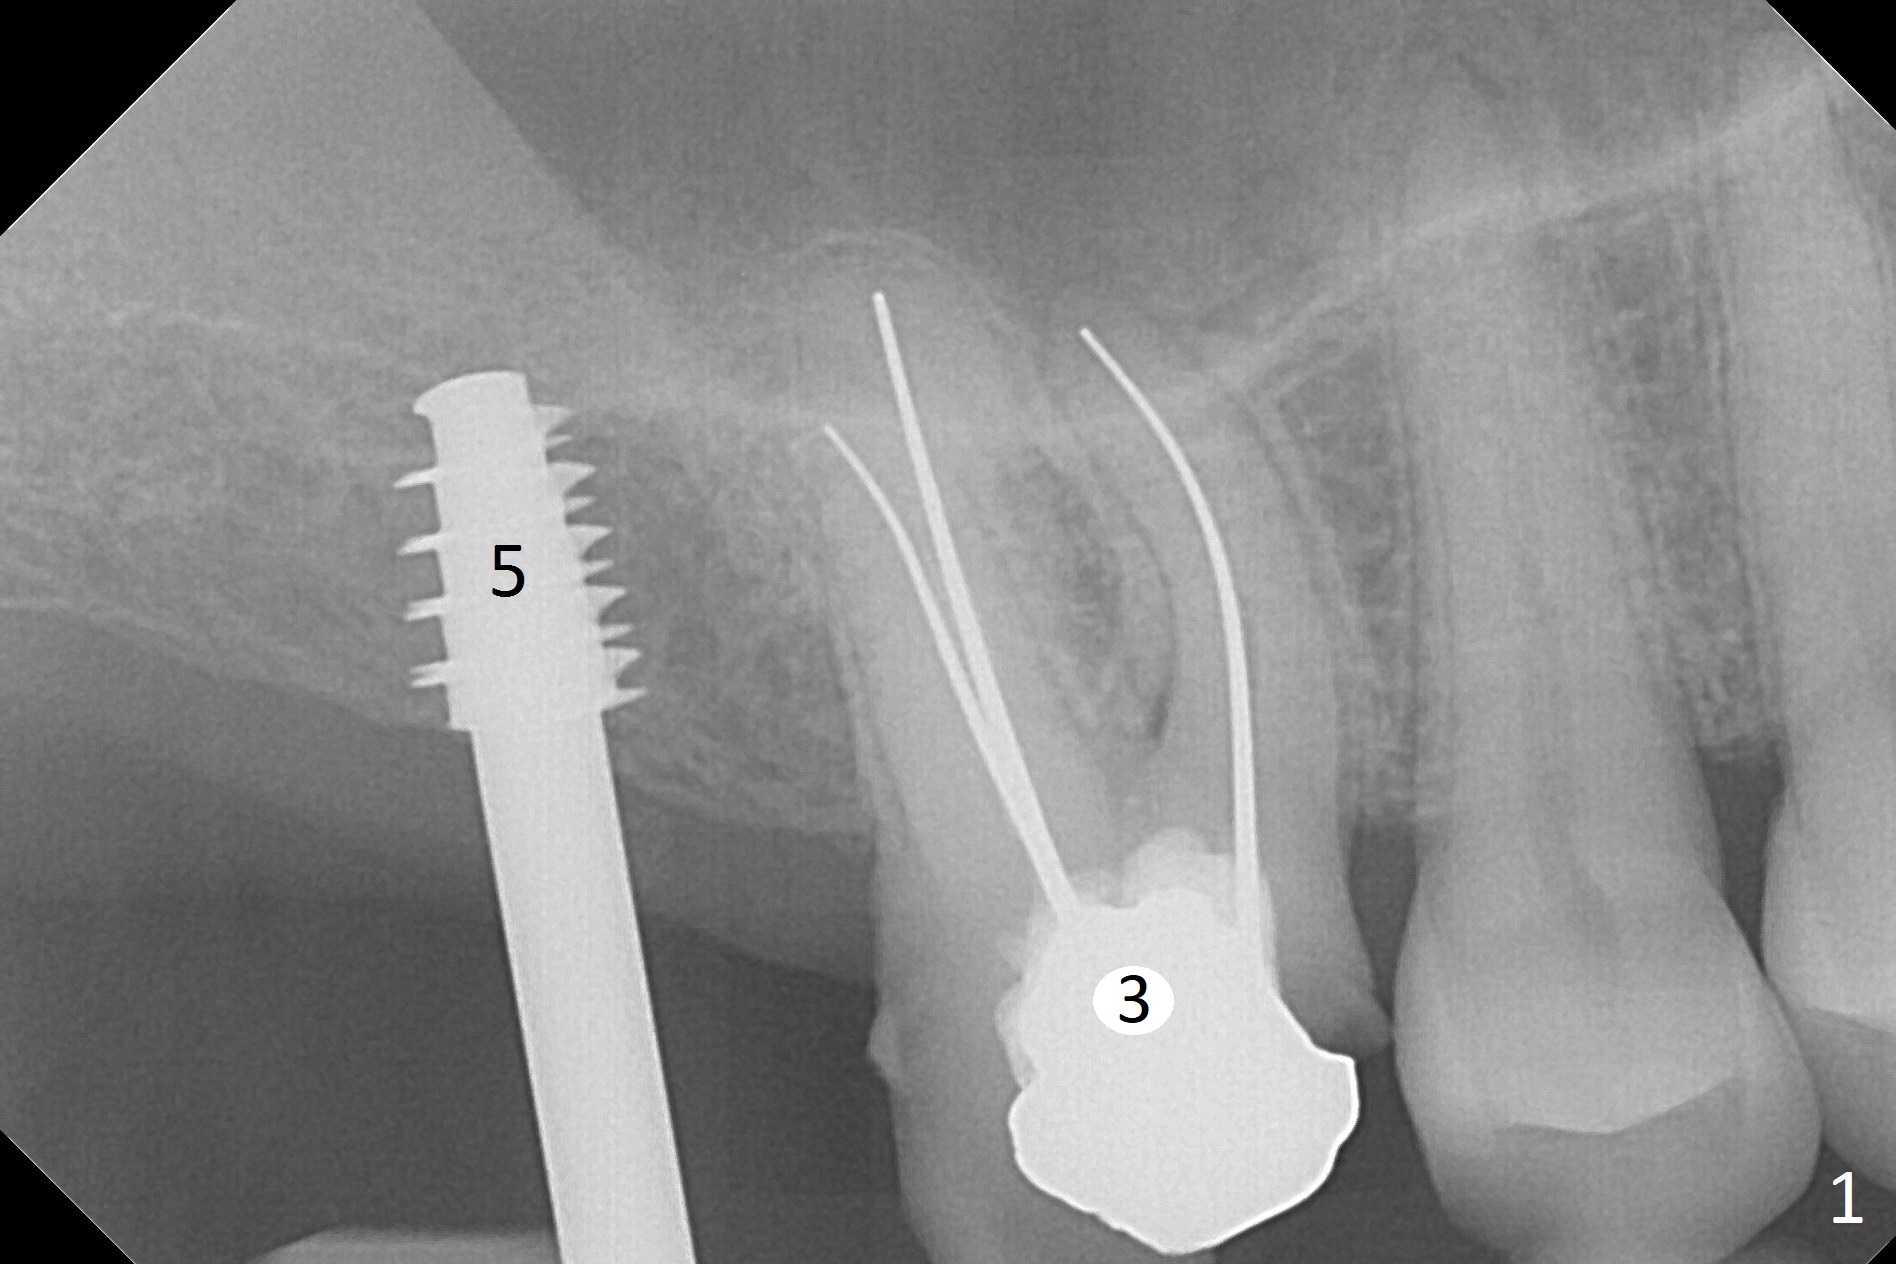

Since the ridge is wide at the site of #2, Magic Split is used for access (flapless) and bone expansion. The bone is so soft that there is no resistance until 4.3 mm Magic Expander is used for 9 mm (Fig.6). A 5 mm tap drill is stable (Fig.1), so are a 5.5x9 mm dummy implant (Fig.2) and a 6x9 mm IBS implant (Fig.3 (<: sinus lift)). In fact the distal thread is still supracrestal (Fig.4 (BW)). After additional 2 mm placement, the distal thread is subcrestal (Fig.5); the mesial margin of a 6.5x4(4) mm abutment is subgingival. A longer cuff (5 mm instead of 4 mm) is more favorable for future restoration. At present the abutment (Fig.7) as well as the tooth #3 with rugged surfaces is used to hold periodontal dressing in place. The abutment margin is completely subgingival 3 months postop (Fig.8 (white dashed line: gingival margin)). It appears that the implant is placed ~ 1 mm deeper than ideal (Fig.9). Diode laser is used for gingivectomy prior to impression. The abutment screw becomes loose 2 months post cementation. After retightening, occlusal equilibrium is conducted with 3 layers of articulating paper. Night guard is provided. The crown/abutment dislodges 1 year 2 months later. Since the gingiva is erythematous, a 6x7 mm healing abutment is placed (Fig.10). The implant seems to have been placed too deep and palatal. It appears that an abutment driver should be buried to prevent the screw re-loosening. Guided surgery should have been done.